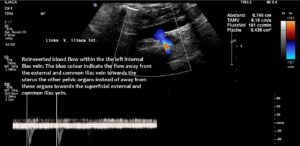

- Subtotal compression of the left common iliac vein with clinical consequences as frequent voiding, severe menstrual pain and pain and heaviness of the left leg- May-Thurner syndrome

The attempt to redirect the pressurised blood from the left renal vein via the left ovarian vein towards the pelvis proved unsuccessful due to the obstructed outflow from the left pelvic hemisphere, a consequence of the compression of the left common iliac vein (May-Thurner syndrome).